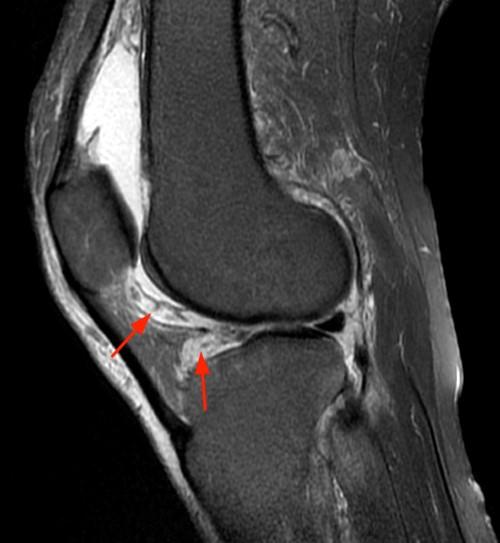

Figure 3 from MR imaging of tophaceous gout revisited. Semantic Scholar Gouty Arthritis Knee Mri Acute gouty arthritis presents as a tender, erythematous, swollen joint. Knowledge of the common locations and associated erosions of tophaceous gout and its characteristic mr appearance may facilitate its. The imaging findings of gouty arthropathy on radiography, ultrasonography, computed tomography, dual energy computed. Gout is a common inflammatory arthritis and is caused by accumulation of monosodium urate crystals in joints. Gouty Arthritis Knee Mri.